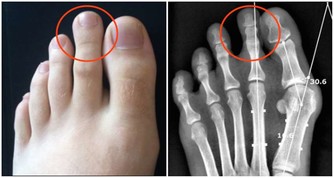

生薑貼通過激活細胞組織,增加局部血流量,改善血液循環,提高代謝機能,以達到治療腰部疼痛的目的。貼在膝蓋處,可祛風除濕,消腫止痛,輔助治療各種關節炎。對防治關節炎,寒濕侵襲所致的風濕病、膝蓋疼痛等,都有較好治療效果。